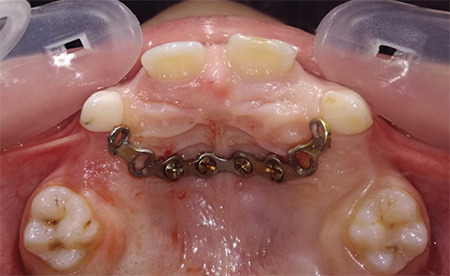

Objective: To evaluate a newly designed minimally invasive palatal-plate face mask combination for the management of developing Class III malocclusion due to maxillary deficiency.

Methods: A sample of 16 Class III patients due to maxillary deficiency in the early mixed dentition (8 boys and 8 girls) aged between 7 and 9 years participated in this study and were treated with a combination of palatal plate face masks. Extra-oral elastics were attached between the intra-oral and extra-oral appliances; the elastics were set at 30° to the occlusal plane. The force magnitude was 250-300 g per quadrant. Cephalometric radiographs were taken before and immediately after maxillary protraction. In addition, skeletal measurements were measured, tabulated, and statistically analyzed. The pre- and post-protraction measurements were compared using the Student's t-test, and the significance level was set at a p-value <0.05.

Conclusion: The palatal-plate facemask combination is an effective treatment alternative for Class III malocclusion due to maxillary deficiency with minimal pain and discomfort.